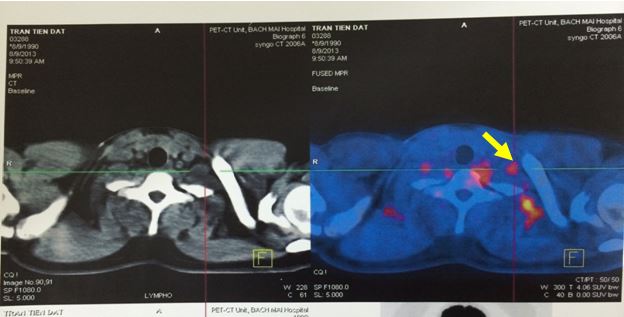

- Trên PET/CT còn tổn thương hạch thượng đòn T 2 cm max SUV 4,3.

Hình ảnh hạch thượng đòn còn lại sau 4 đợt hóa chất R CHOP.

Tổn thương hạch ổ bụng còn lại trên CT sau R- CHOP x 8.

Sau khi được chụp PET/CT, có điều đặc biệt ở bệnh nhân này là tổn thương hạch ổ bụng phát hiện trên CT lại hoàn toàn không tăng hấp thu FDG, mà bệnh nhân lại được phát hiện thêm một tổn thương tăng hấp thu FDG bất thường ở đầu xương ức. Các vị trí khác trong cơ thể không có tăng hấp thu FDG bất thường.

Tổn thương hạch ổ bụng hoàn toàn không hấp thu FDG.